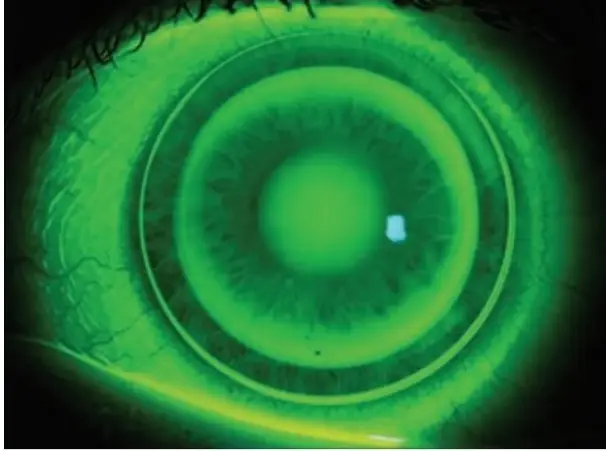

下圖為配戴硬式隱形眼鏡的角膜螢光染色,下列敘述何者錯誤?

A螢光染色呈現標準的牛眼型態,為角膜塑型片,可矯正近視

B螢光劑堆積的中央區,顯示鏡片的基弧較角膜陡

C鏡片定位良好、對稱,適當的邊弧翹角(edge clearance )有利於淚液交換

D中心旁區沒有螢光液堆積的區域,是角膜塑型片將角膜上皮壓平的設計

本題考驗光師對硬式隱形眼鏡(尤其是角膜塑型片,orthokeratology lens)螢光染色圖型(fluorescein pattern)的判讀能力。角膜塑型片採用「反幾何設計(reverse geometry design)」,螢光染色呈現典型的「牛眼型態(bull's eye pattern)」,由中心向外分為四個區域,各區域的螢光亮暗反映鏡片弧度與角膜的距離關係。本題為反向題,問「何者錯誤」。

圖片在鈷藍光(cobalt blue light)照射下顯示螢光素鈉(sodium fluorescein)染色影像,可見標準的角膜塑型片牛眼型態,由中心向外依序如下:

中央暗區(central dark zone):中央約 4 mm 的較暗區域,代表鏡片基弧(base curve)與角膜之間的淚液層極薄(< 15–20 μm),即「中央貼觸區(central bearing)」,螢光液少 → 顯示較暗。此區為鏡片壓平角膜上皮的主要作用區,是塑型效果的核心。

中旁亮環(mid-peripheral bright ring):中央暗區外圍一圈明亮的螢光綠環,對應鏡片的反弧區(reverse curve / tear reservoir zone)。此區弧度比基弧陡峭,離開角膜面,形成淚液儲蓄池(tear res